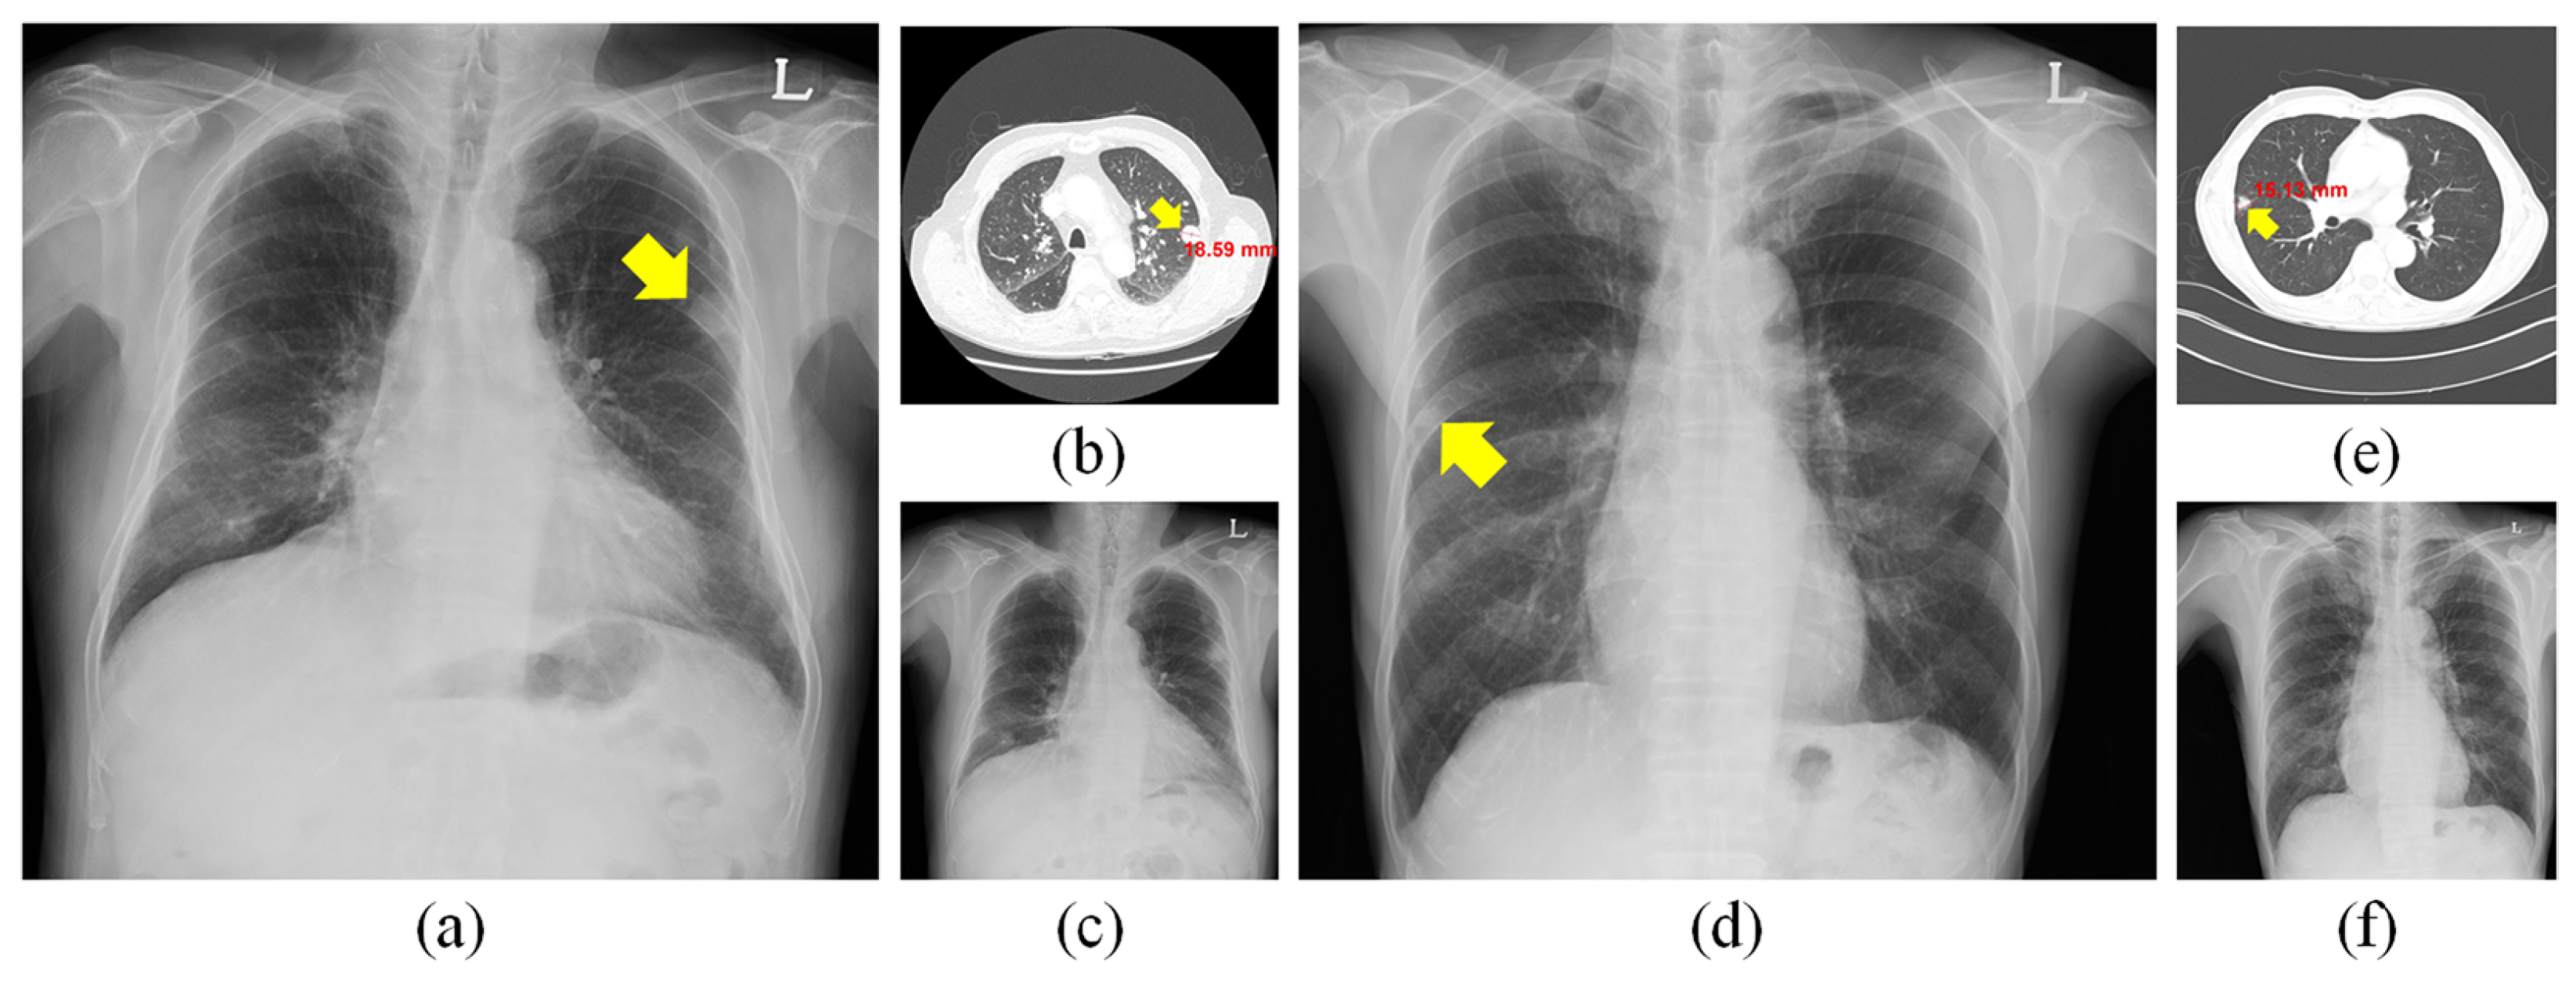

3.1. Software

3.1.1. Training Data

3.1.2. Model Architecture